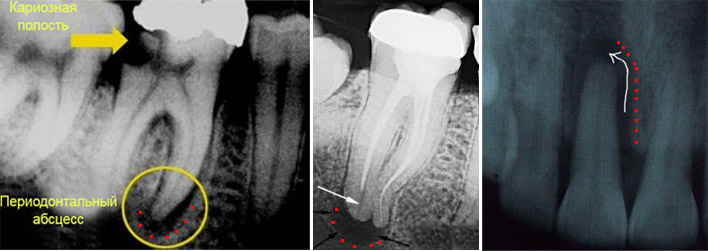

Наиболее часто болезнетворные бактерии попадают в корневой канал зуба при запущенной форме пульпита. В этом случае инфекция направляется через кариозную полость в пульпу зуба, проходит через отверстия корневых каналов и таким образом попадает в периодонт, вызывая в нем образование периодонтального абсцесса (гнойного мешочка).

Нередко встречается периодонтит, возникший в результате некачественно запломбированных каналов зуба (ятрогенная причина). Если при лечении пульпита пломбировка корневых каналов была произведена не до верхушки корня, то в незапломбированной части возможно развитие инфекции с последующим ее выходом за пределы зуба. Таким образом, возникает периодонтальный абсцесс у верхушки зуба.

Хронический гранулематозный периодонтит характеризуется образованием периодонтального абсцесса (мешочка с гноем). При отсутствии правильного лечения развиваются следующие стадии: гранулема (диаметр до 0,5 см), кистогранулема (диаметр от 0,5 до 1 см) и киста (диаметр более 1 см). Рост мешочка при хроническом периодонтите гранулематозной формы происходит за счет постоянного увеличения гноя внутри оболочки, что вызывает давление на костную ткань и ее рассасывание.